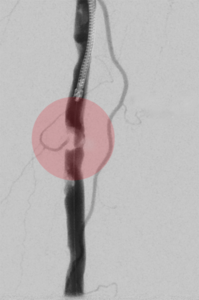

5. Thrombektomie – mechanische Entfernung von Blutgerinnseln

Wenn ein Gefäß durch Blutgerinnsel verschlossen ist, kann man den Verschluss mechanisch wiedereröffnen, indem man die Ablagerungen über spezielle Katheter absaugt. Dazu stehen uns Kathetersysteme, die mit Vakuum arbeiten bzw. zusätzlich die Gerinnsel vor dem Absaugen mit Hilfe von Wasserstrahlen oder Rotation der Katheterspitze zerkleinern, zur Verfügung.